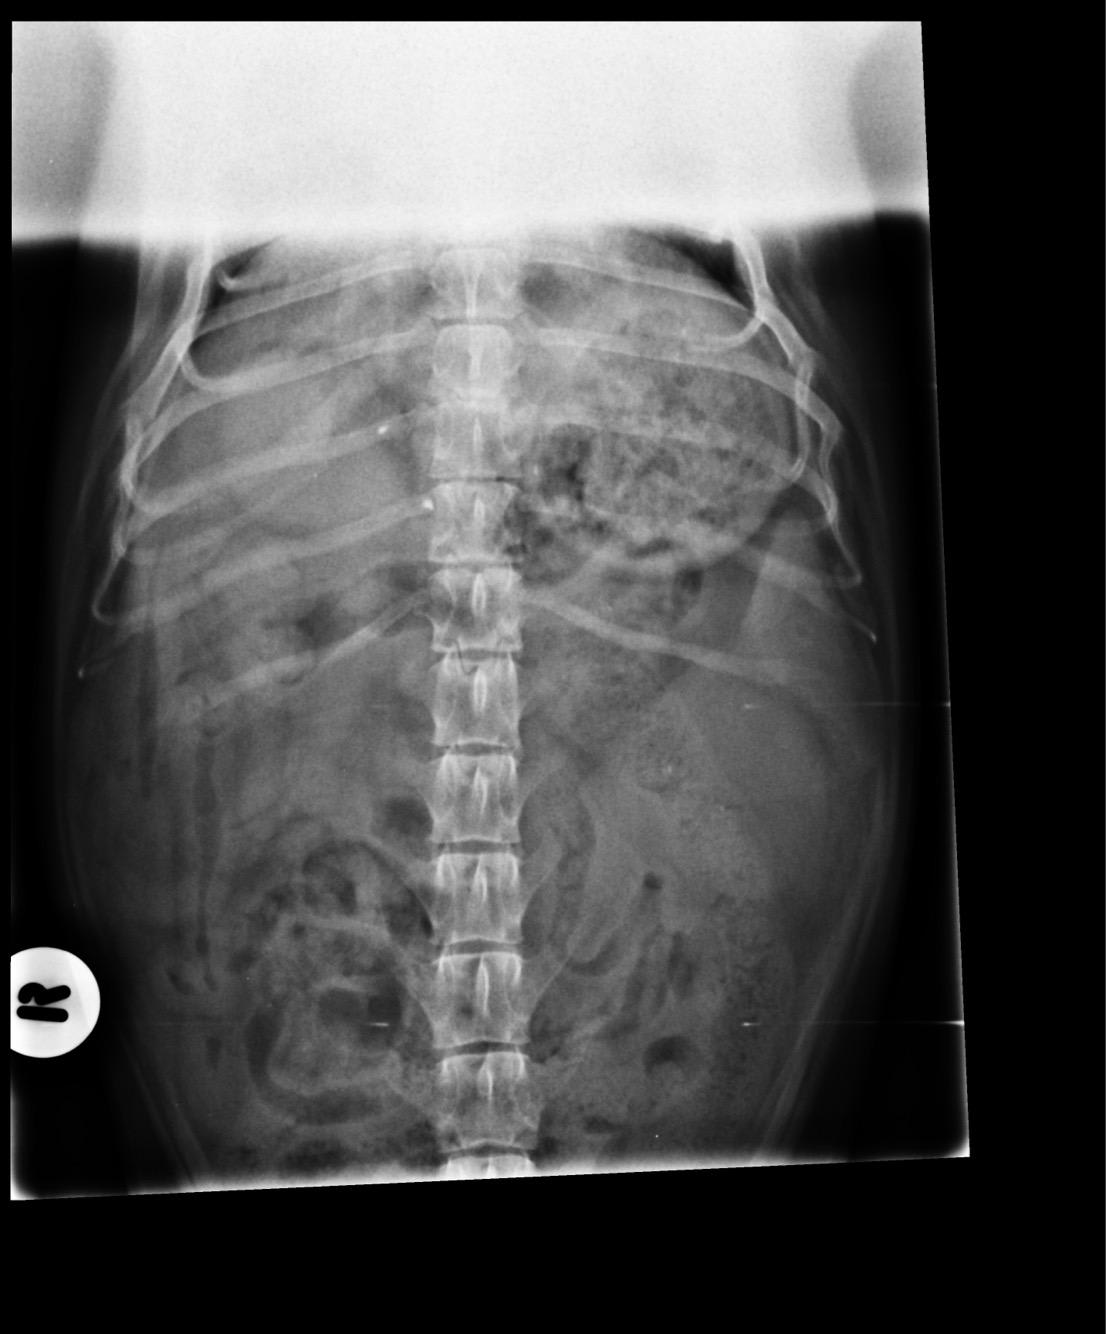

Pet's info: Dog | Dachshund | Male | neutered | 6 years and 6 months old | 20 lbs

Could you please tell me what you see in this X-ray and what we should do next? Thank you

It is not recommended to interpret x-rays without information about that is going on with the patient. If you would like to post more information about what is going on with Rolo, one of us will be happy to try to help you.